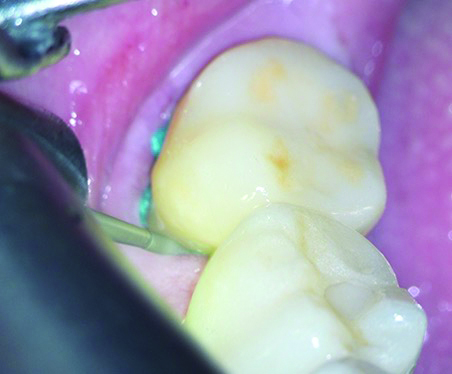

Fig 6. After the rounded shoulder margins were defined, the approximal contact was broken, with a wedge-matrix combination protecting the adjacent tooth. This was done under full microscopic control.

Figure 6

To begin the tooth preparation, depth cuts were made first on the vestibular aspect and then on the distal and occlusal areas using a depth indicator bur (Figure 3). These cuts were then marked with a pencil to ensure a minimally invasive preparation of 1 mm (Figure 4). Next, the grooves were connected around the entire tooth structure using a round-end diamond bur (Figure 5). The rounded shoulder margin was then defined on the vestibular aspect based on the previously marked finish line, extending distally while maintaining a 0.5-mm depth coronally. Under full microscopic control, the clinician carefully broke the proximal contact while a wedge-matrix combination was used to protect the adjacent tooth (Figure 6).